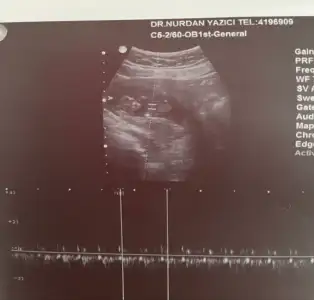

Merhaba. Bu ultrasonların yönünü algılama konusunda sorun yaşıyorum kafam biraz karışıyor kamera işin içine girince yönü değişiyor aslında sanırım.Şimdi daha detaylı da araştırdım bunu aslında sizin bebek resimde solda ama aslında sağda duruyor. Yani Erkek. konuyu açan arkadaşa da yanlış söylemiş oluyorum bu durumda.Vajinal ultrason aynalı gösteriyor diyorlardı burda hep ama araştırınca karından ultrasonun aynalı gösterdiğini öğrendim. Rami Teorisine göre bebeğiniz Erkek.